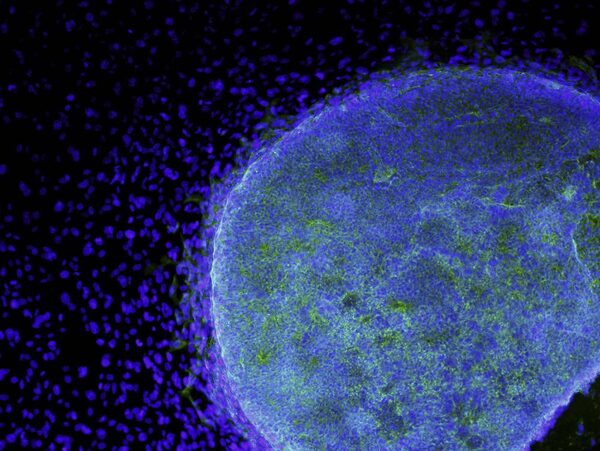

A microscopic view shows a colony of human embryonic stem cells (light blue) growing on fibroblasts (dark blue).Alan Trounson/California Institute for Regenerative Medicine/Reuters